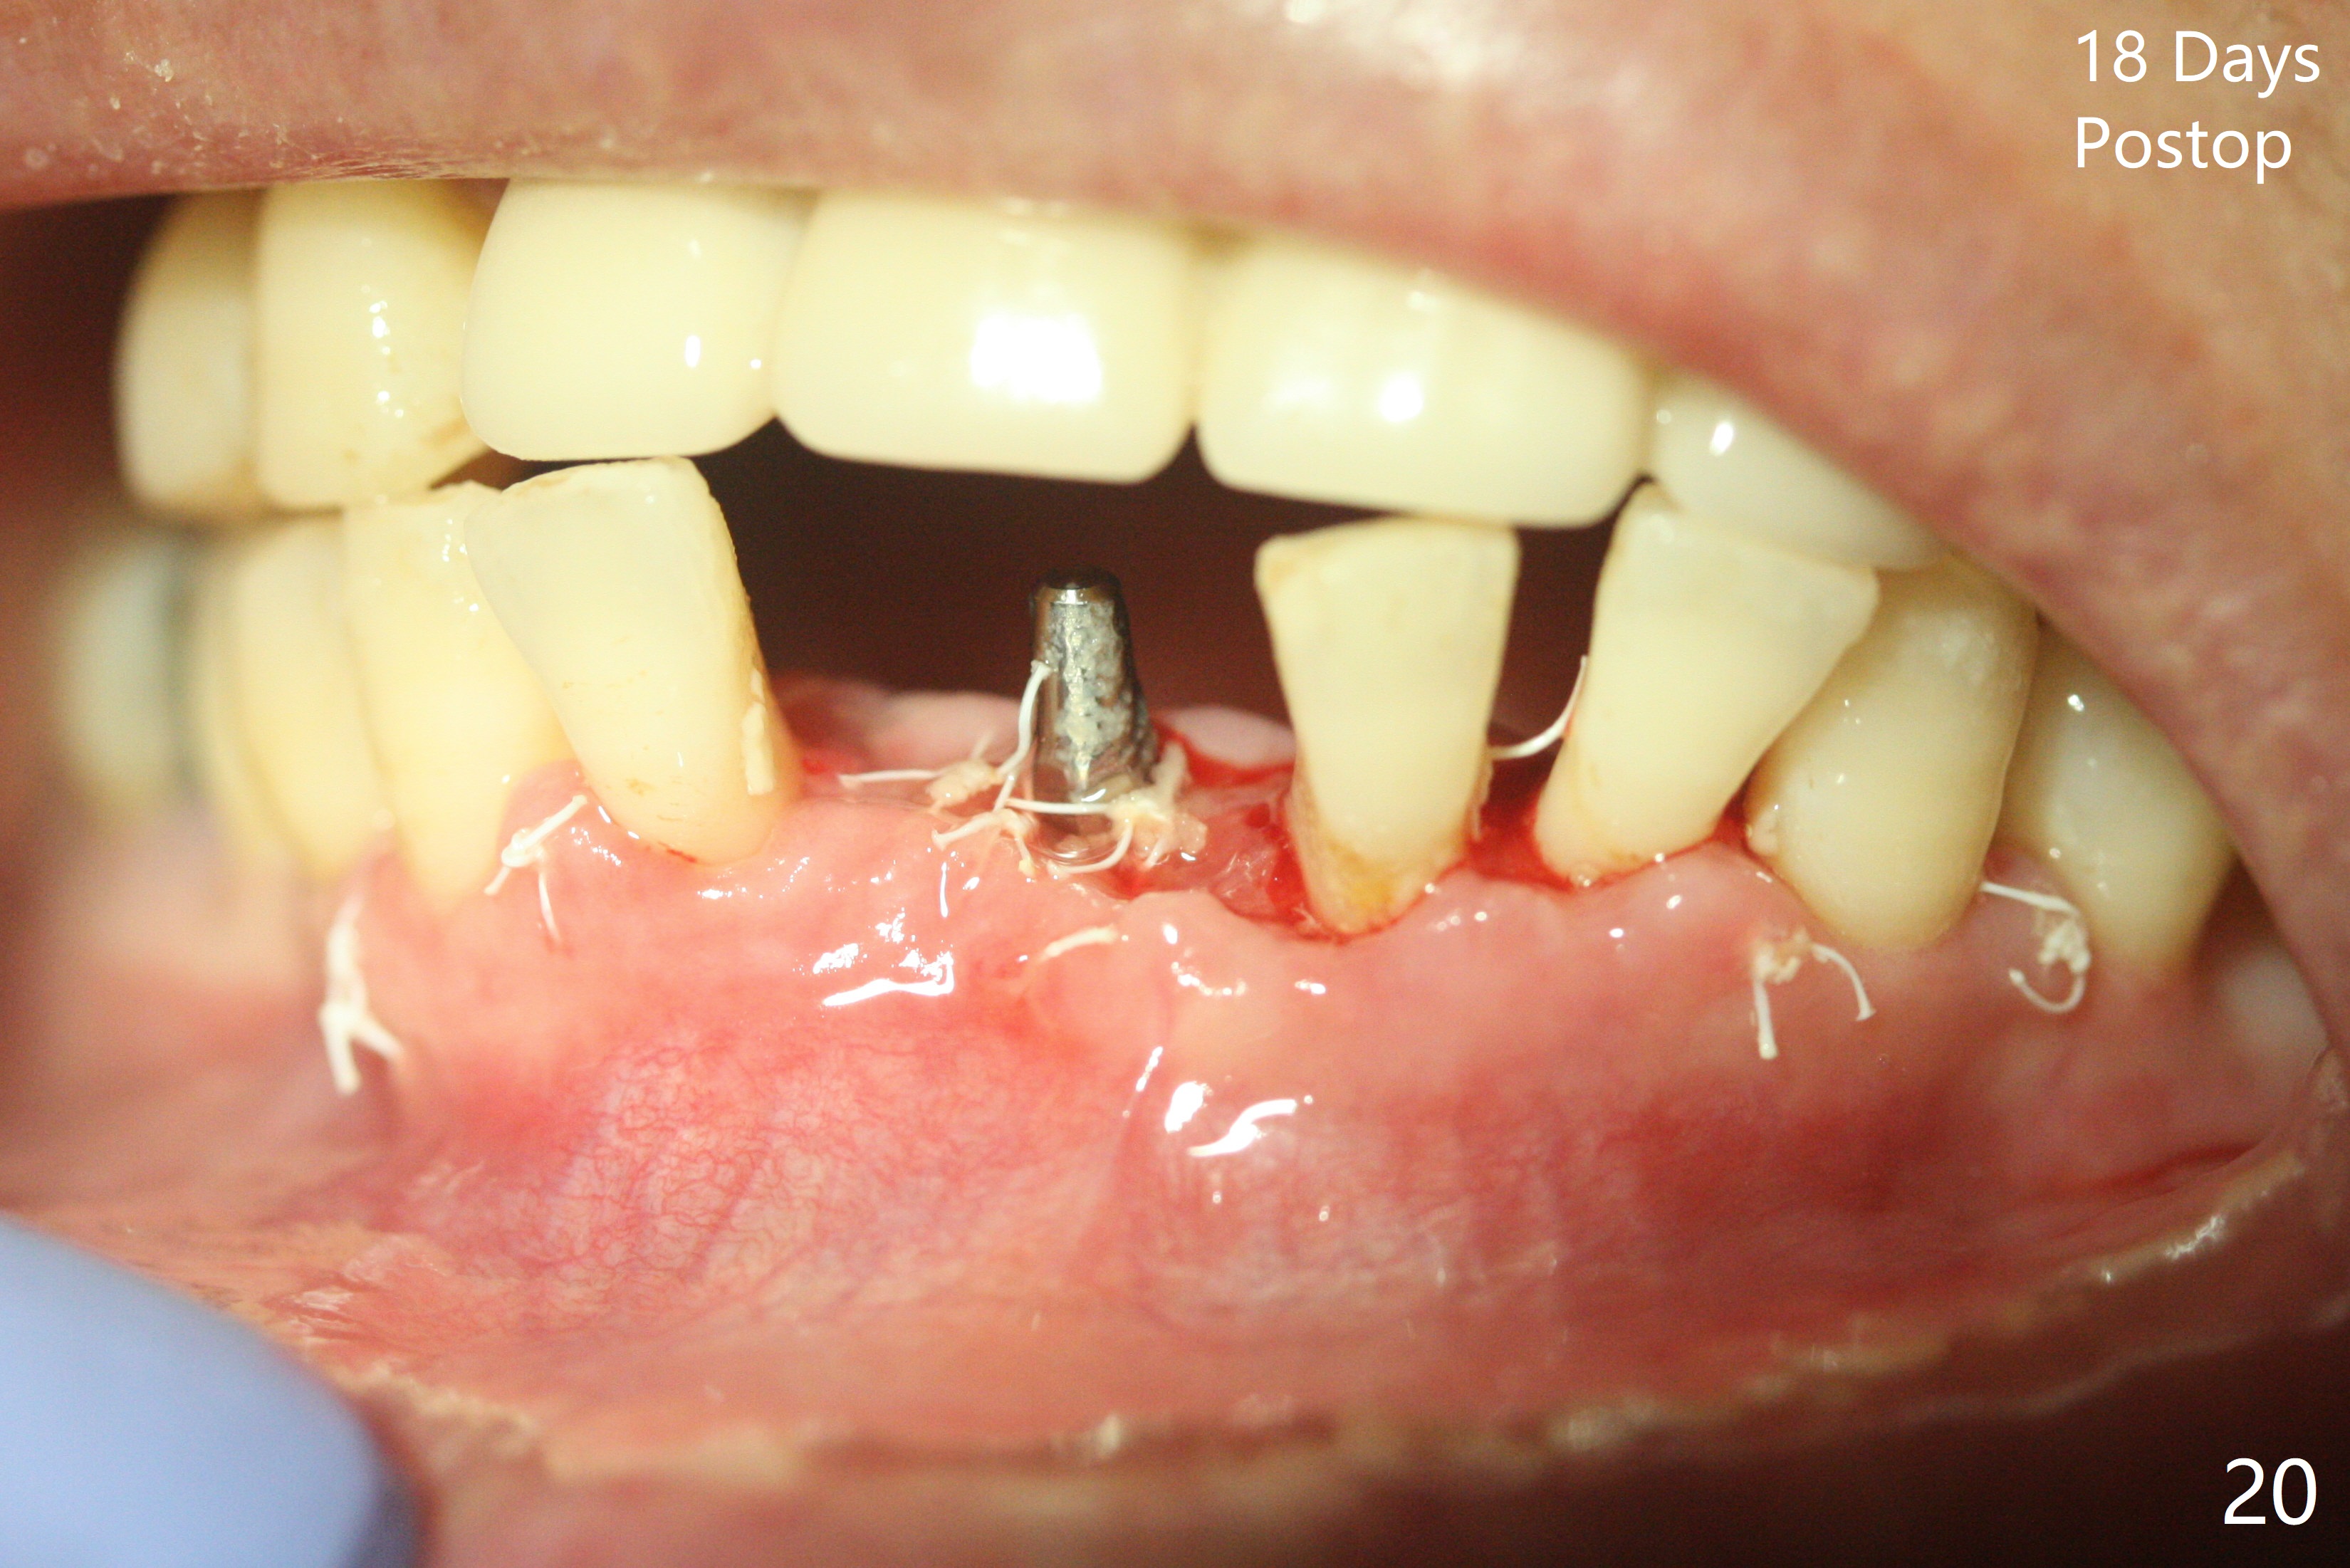

56岁女十分恐惧治疗,缺失右下1,其余切牙由于骨质吸收颊侧移位(图一:1,2),但是她不愿意拔除,同意右下1种植,牙周骨手术,植骨;植体整合后作为支抗,矫正移位下门牙。为了防止忘记舌侧瓣分离,先做舌侧切口(图二),然后颊侧瓣松弛分离(图三),包括使用前牙隧道刀(图四)切断颊侧骨膜,松弛到颊侧瓣能向舌侧牵拉3-4毫米(图五),舌侧瓣骨膜下广泛,深部分离(好像不能切断骨膜,图六),放置导板,磨平狭窄的牙槽嵴(图七:O(osteotomy)),植入2.5x12(4)毫米一段式植体(图八:故意舌侧植入,以便以后矫正),在颊侧骨板打多个出血洞(图八:箭头),然后把在平的器皿上形成的粘性骨板(sticky bone,图九),放置于植体和移位切牙周围(图十),接着使用消毒过的橡皮障punch(图十一(纸头相当于PRF膜;事先给助手示范))在三个PRF膜(图十二)打洞,套在植体和门牙上(图十三: 箭头),防止膜(图十四)和骨块(图十五,十六:*)移位,最后还必须使用最原始方法牙周敷料保护伤口(图十七)。术后9天,舌侧牙周敷料脱落,伤口稍微裂开(图十八)。术后18天撤除敷料,伤口裂开处有新鲜肉芽组织生长(图十九(*:下面是填入的骨粉,将是增宽的牙槽嵴(如果你是乐观主义者)),二十)。病人十分感激我们帮助她度过难关。她的确有sleep apnea,否定tongue thrust。术后三个月植体周围没有明显骨质吸收(图二十一至二十三),左下1,2轻度反合(图二十四),植体周围软组织健康(图二十五),5-5安置矫正器(图二十六,二十七,12 niti)。一周后下切牙向舌侧移动(图二十八),左下1,2反合纠正(图二十九)。再一周变化不大(图三十),植牙圈有些松动,两周后将重做临时牙冠,槽往舌侧移动。结果病人提前回来,植牙槽舌侧移位。一周后右下2不适(图三十一),尝试近中牵引(图三十二)。